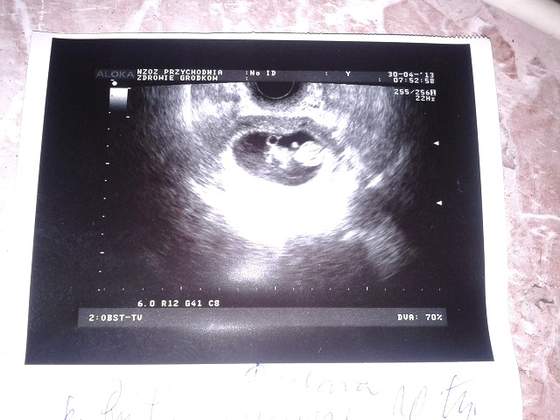

byłam już na usg 2 razy - dzidzia się zagnieździla, a na drugim już było widać serduszko!